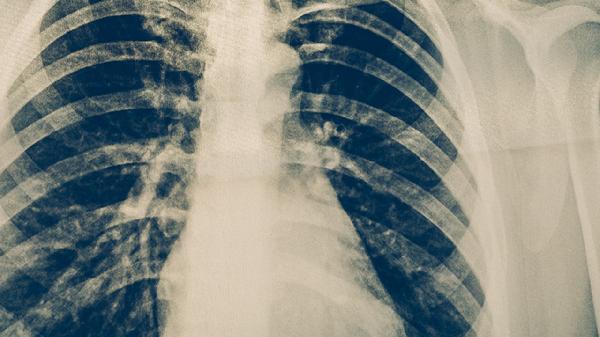

磨玻璃结节是肺部CT检查中常见的影像学表现,呈现为云雾状密度增高影。当结节内出现空气管征时,通常表现为支气管穿过结节内部或边缘,这种征象在早期肺癌中较为常见。空气管征的形成可能与肿瘤细胞沿支气管壁生长有关,导致支气管未被完全堵塞而保持通畅。这种情况下,结节可能为原位腺癌或微浸润性腺癌,属于肺癌的早期阶段。

除早期肺癌外,磨玻璃结节伴空气管征也可能由其他原因引起。肺部感染如肺炎、肺结核等炎症性疾病在吸收过程中可能形成类似表现。部分良性病变如肺内淋巴结、局灶性纤维化等也可能呈现这种影像特征。这些情况通常需要结合临床表现、实验室检查和其他影像特征进行鉴别。